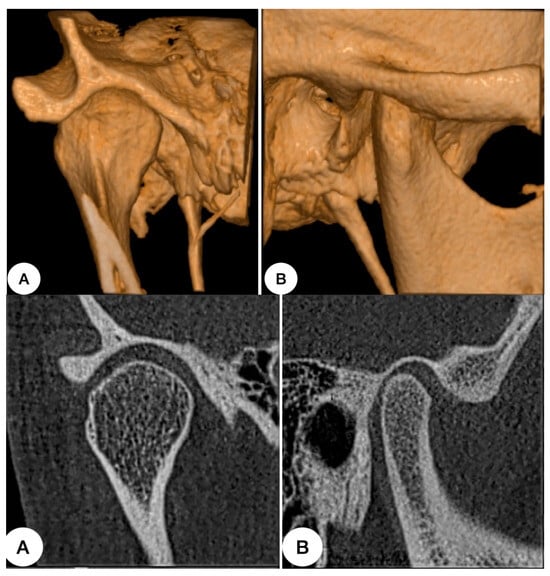

The TMJ is a complex joint system, sensitive to changes in masticatory loads and occlusal conditions that can influence the development of temporomandibular disorders [18]. Knowing the biomechanical properties of the components is key to understanding the impact of mastication and occlusal forces on the joint [19]. The articular disk is a structure that plays an important role in maintaining the function and health of the TMJ, helping to coordinate the action between different articular surfaces with load distribution during function [20] (Figure 2).

Figure 2. Author’s case: healthy temporomandibular joint. (A) Frontal section. (B) Sagittal section. Position in the fossa, bone volume, density, morphology, and corticalization is observed in those images.